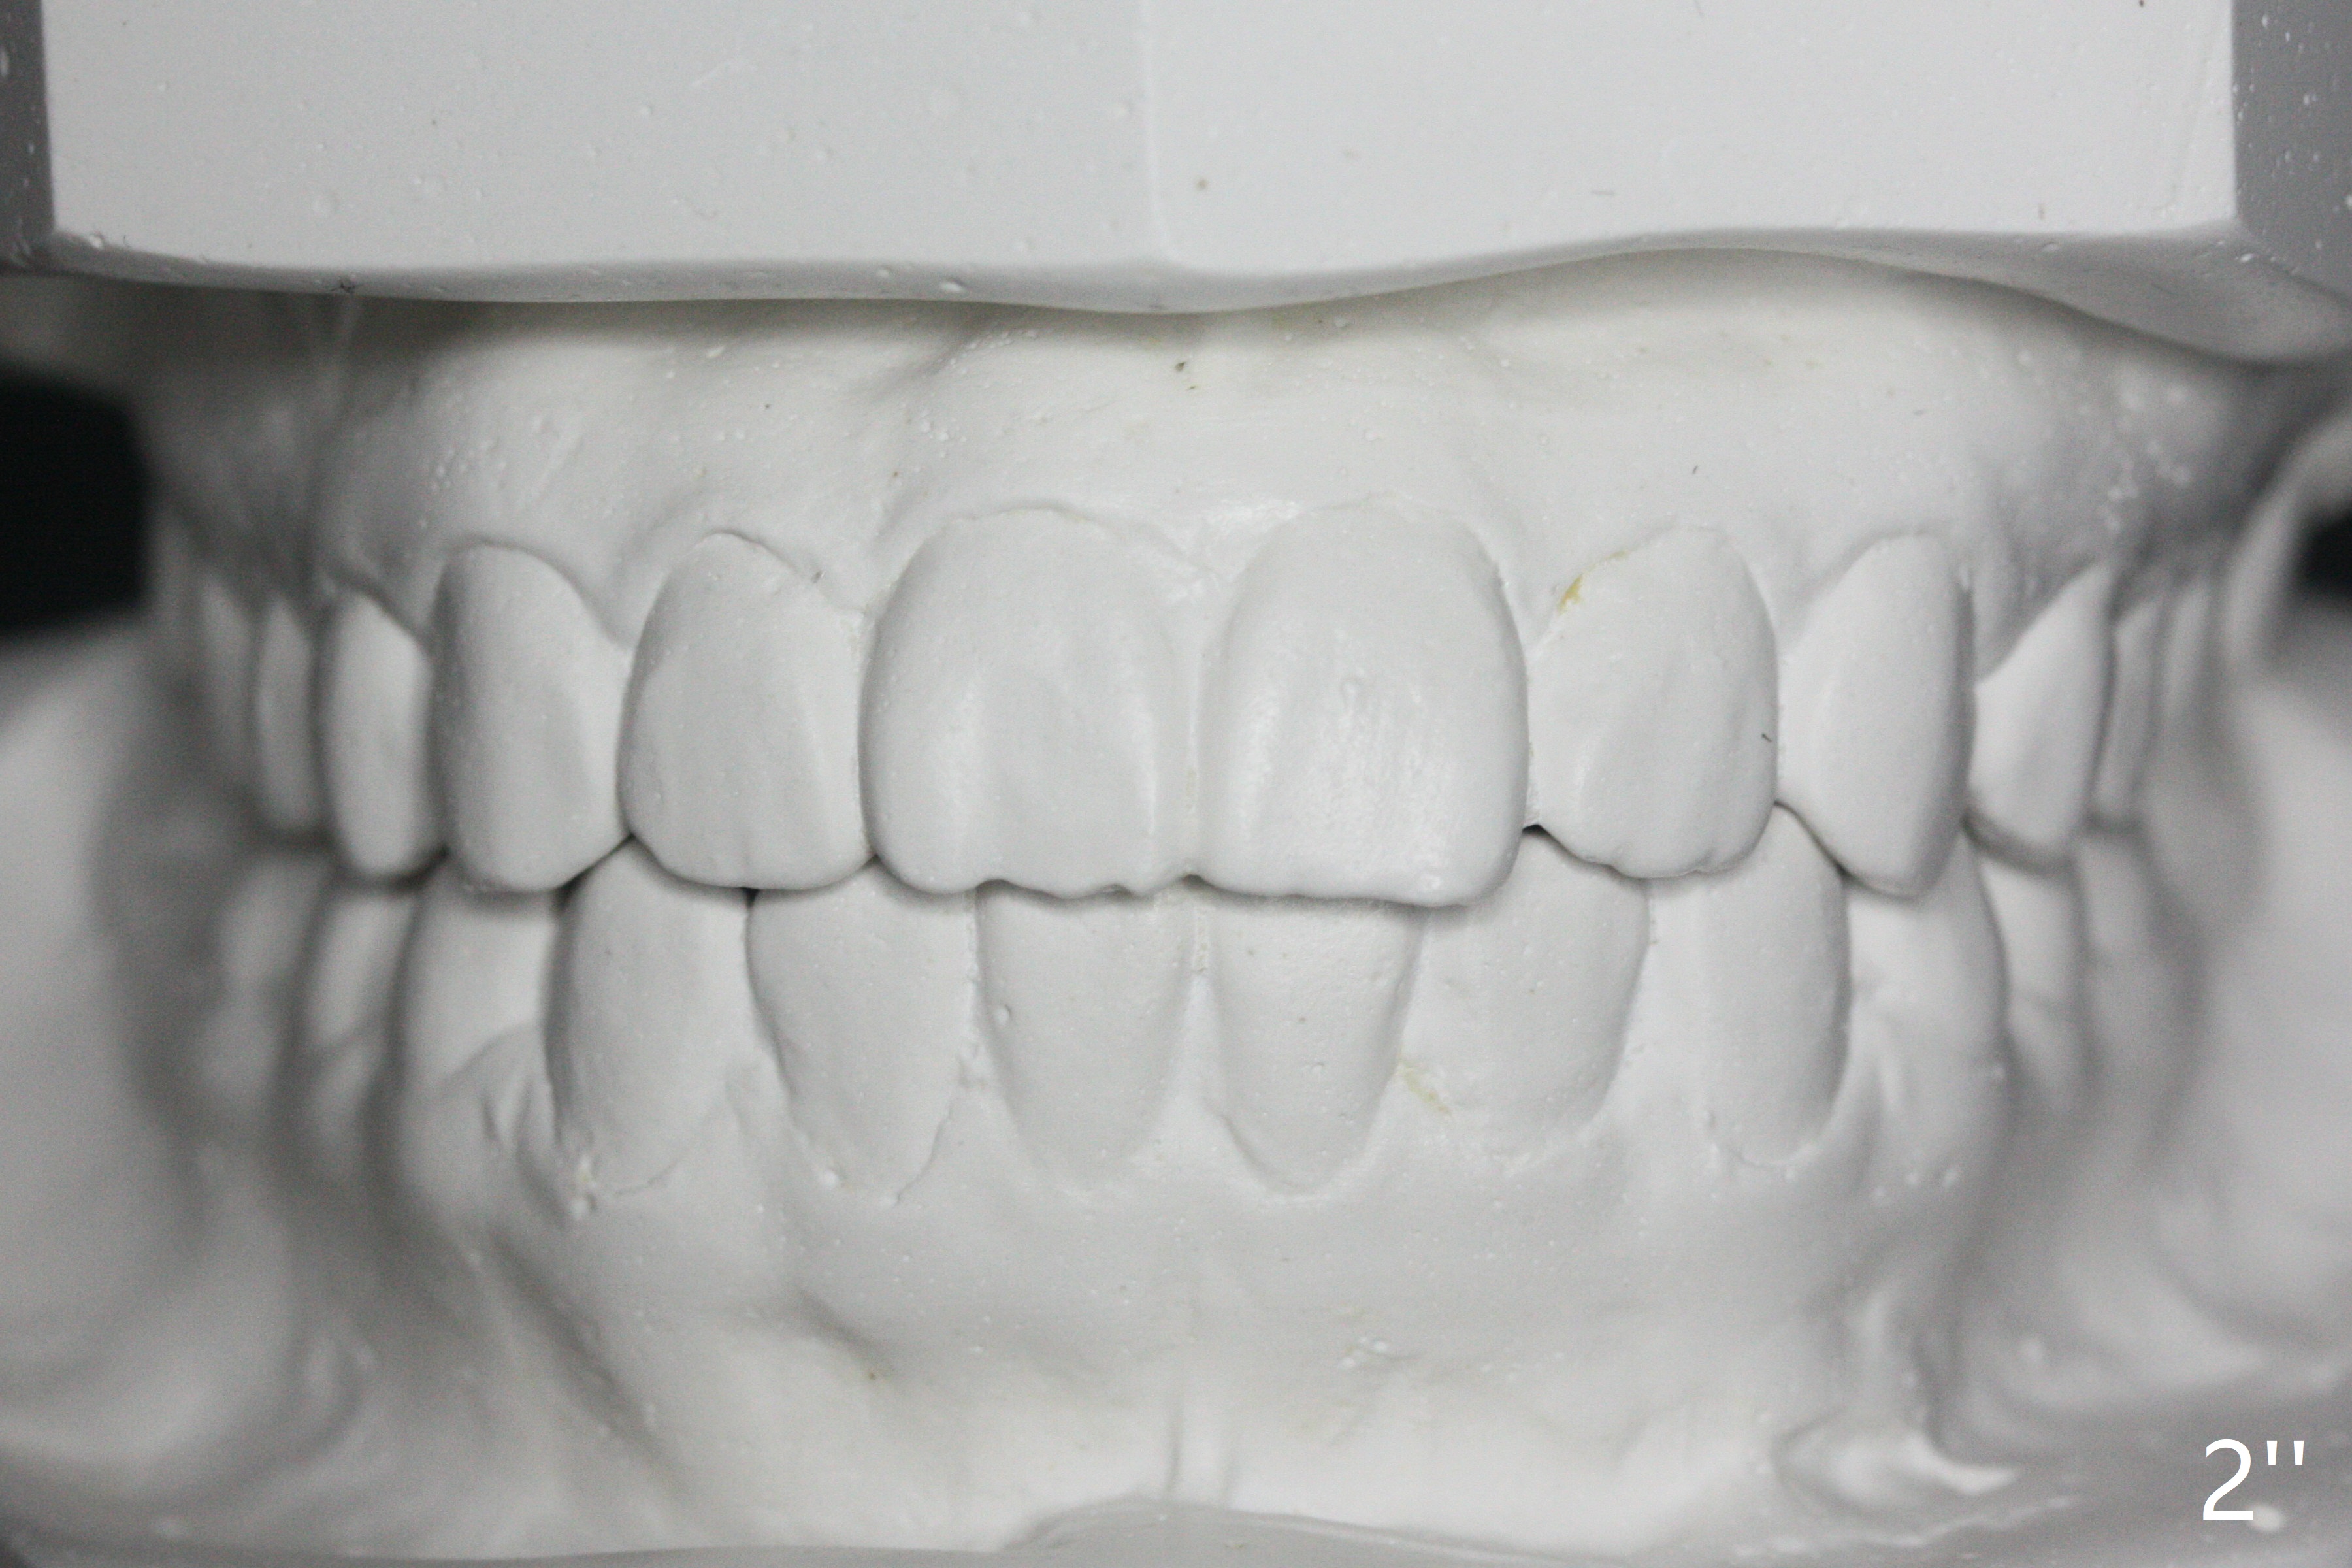

A 12-year-old woman has severe crowding including UL7 impaction (Fig.1-5), finishes non-extraction orthodontics at the age of 15 (Fig.1'-5') and returns for retainer remake at 19 (Fig.1''-5''). Four years post debanding, UL7 (Fig.4') seems to improve its position (Fig.4'').